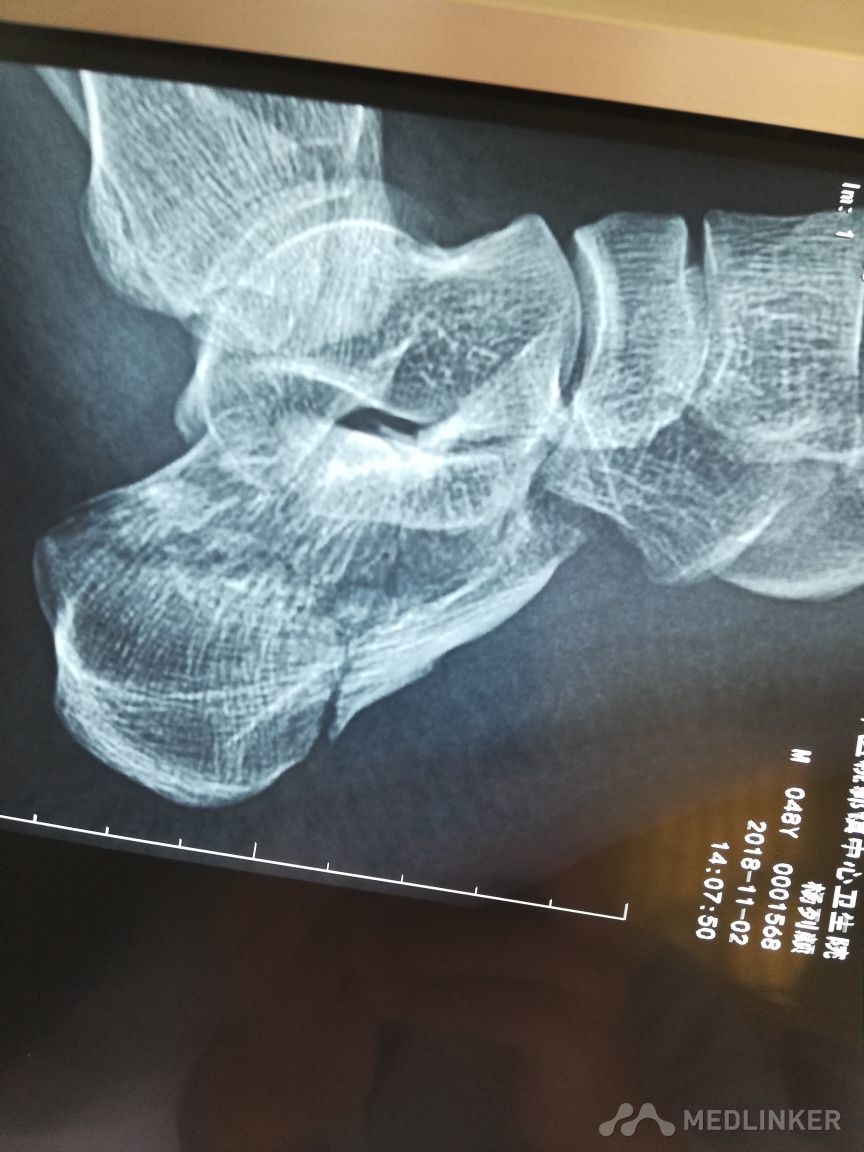

各位老师看看这个跟骨骨折需要手术吗

患者,男,48岁,2天前从高处摔下,伤及左足,拍片见左跟骨粉碎性骨折大家看看是否需要手术治疗,患者不大想手术